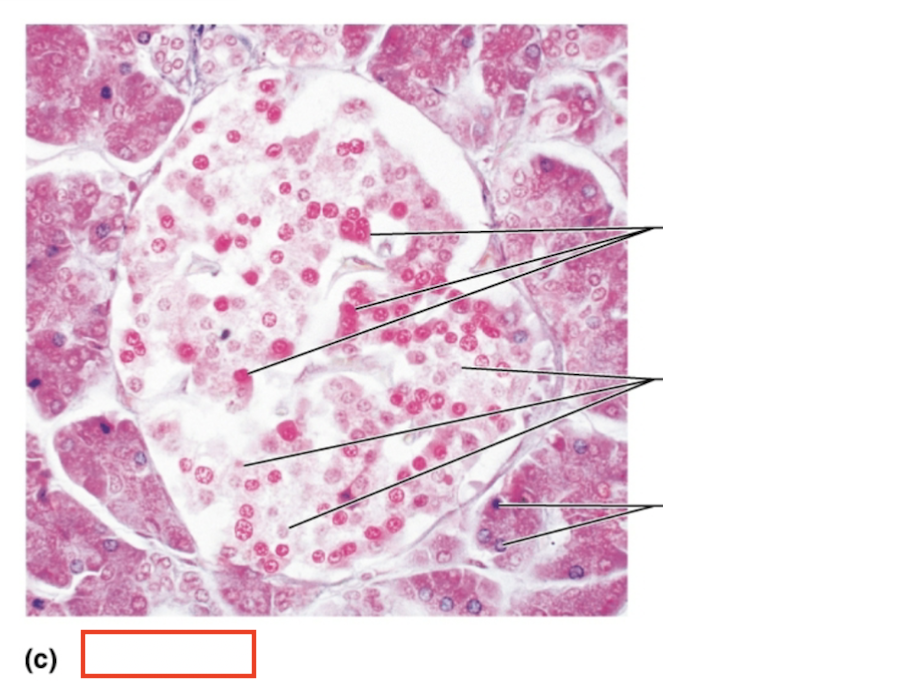

What structure is highlighted?

alpha cells (glucagon producing)

What structure is highlighted?

beta cells (insulin producing)

What structure is highlighted?

pancreatic acinar cells (exocrine)

What tissue is shown?

pancreatic islet